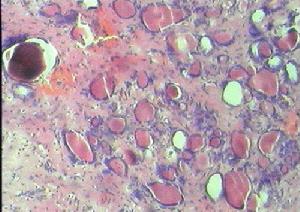

本法對定性診斷有一定參考價值,臨床已廣泛套用。但診斷可靠性取決於穿刺取材技術及閱片經驗。甲狀腺腺瘤的細胞學表現為瘤細胞較小,其形態一致,排列成濾泡狀,核染色質緻密,胞漿少,偶見小核仁。乳頭狀癌,瘤細胞成乳頭狀排列,核明顯畸形,核內可見圓形、大而空亮的包涵體,也可出現酸性合體細胞、砂粒體泡沫細胞,偶見核大小不一,染色質深染,核仁大。濾泡癌與濾泡腺瘤很難鑑別。未分化癌常出現大量瘤巨細胞,核圓或不規則,染色質緻密,胞漿嗜酸性多空泡。

2、濾泡狀癌(follicular carcinoma) 約占15%,多見於50歲左右的婦女。此型發展較快,屬中度惡性,且有侵犯血管傾向。頸淋巴結轉移僅占10%,因此預後不如乳頭狀癌。

4、髓樣癌(medullary thyroidcarcinoma) 少見。發生於濾泡旁細胞(C細胞),可分泌降鈣素(calcitonin)。細胞排列呈巢狀或束狀,無乳頭或濾泡結構,其間質內有澱粉樣沉著,呈未分化狀,但其生物學特性與未分化癌不同,。惡性程度中等,可有頸淋巴結轉移和血運轉移。